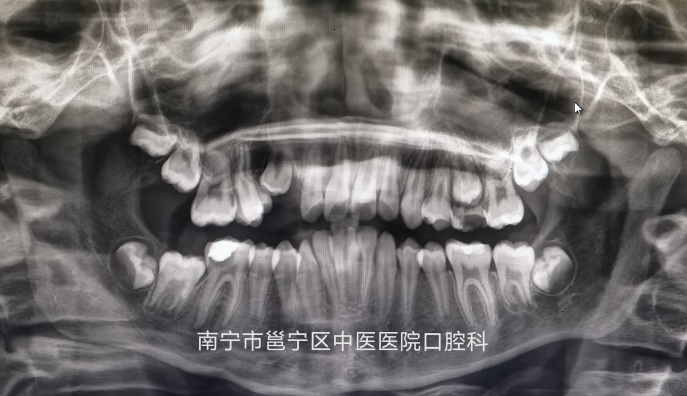

口腔曲面断层X线摄影是通过专门设计的口腔曲面全景摄影X线机,将上颌骨、下颌骨、颞颌关节、上颌窦、鼻腔及全口牙齿的影像同时显示在1张体层照片上的摄影技术。口腔曲面断层摄影在医疗诊断中应用越来越广泛,它能为牙体疾病,牙齿矫治以及牙槽骨,颞颌关节的骨折骨病等多种疾病提供重要的信息。

(长歪的智齿)

通过拍摄全景牙片,我们可以清楚地知道牙冠、牙根、牙槽骨及关节等情况,及时发现问题,处理问题,以免耽误治疗时机。

我院口腔科引进了先进的进口数字化全景及头颅正侧位二合一机,拍摄时间短,成像清晰,可帮助医生快速诊断,欢迎广大患者前来咨询及口腔检查。